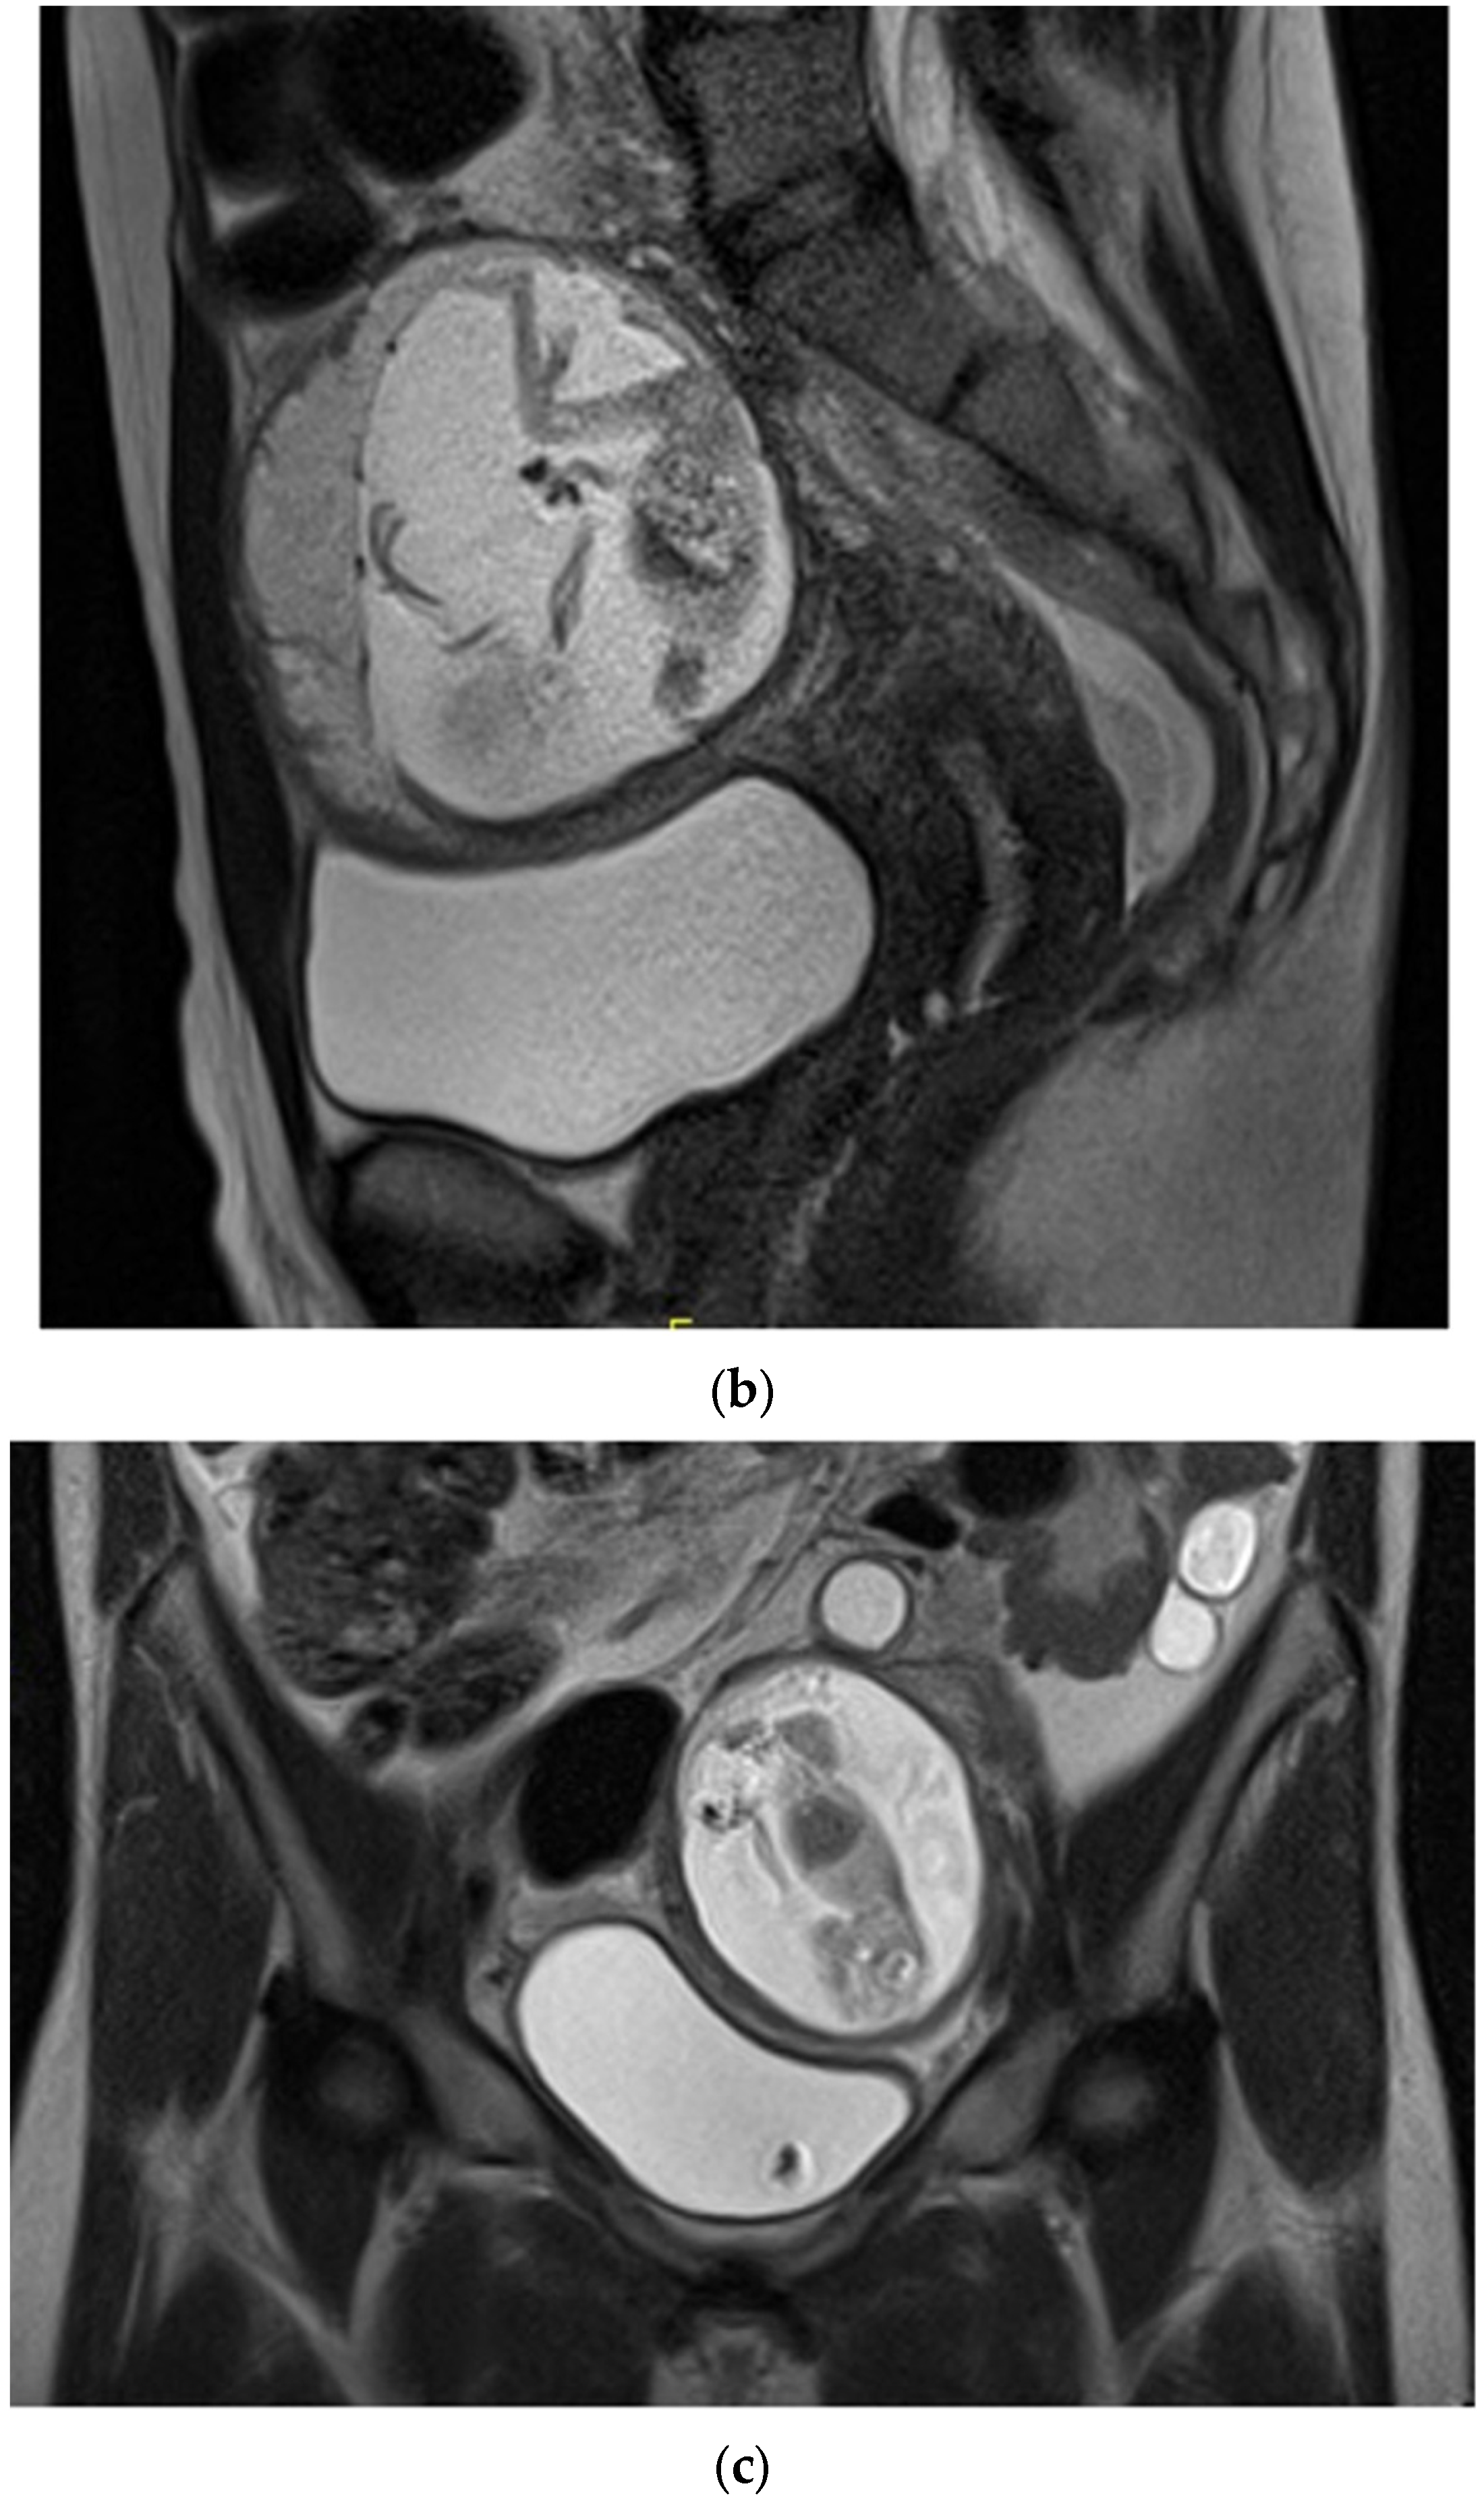

Figure 1.

A 33-year-old female presented with diffuse abdominal pain. Transverse ultrasound of the pelvis through the level of the uterus demonstrating gestational sac outside of the uterus and free pelvic fluid. Estimated live extrauterine gestational age of 13 weeks 6 days +/− 1 week 2 days. It is unclear whether the ectopic pregnancy is located within the left fallopian tube or involves the left ovary.